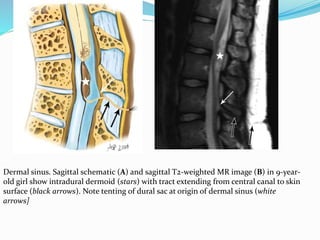

Dermal sinus. Sagittal schematic (A) and sagittal T2-weighted MR image (B) in 9-year-

old girl show intradural dermoid (stars) with tract extending from central canal to skin

surface (black arrows). Note tenting of dural sac at origin of dermal sinus (white

arrows]

 Dermal sinus; It is an epithelial lined fistulous

communication between CNS or its meningeal

covering and skin. It results from focal incomplete

disjunction between neuroectoderm and cutaneous

ectoderm

 It may be associated with intraspinal dermoids or

epidermoids which show variable imaging findings

depending on their contents

 Dermoids usually appear hyperintense on both T1 and

T2 weighted images while epidermoids are

hypointense on T1 weighted and hyperintense on T2

weighted images

 CNS infection is a common complication because of

fistulous communication and hence these cases

require early surgical repair